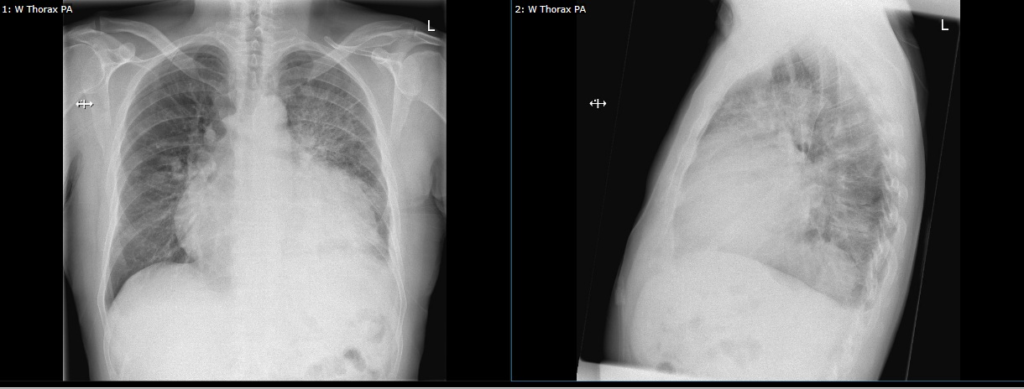

Figuur C: thorax röntgen foto